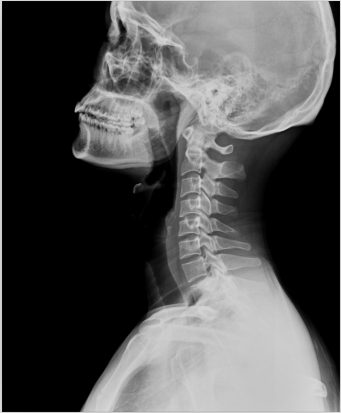

2、頸椎腰椎——最佳選核磁共振成像、次選CT

頸椎病、腰椎間盤突出等椎間盤疾病需要觀察椎間盤與相應(yīng)的神經(jīng)根,要想更好觀察這些軟組織,最優(yōu)選擇就是磁共振成像。同樣,對(duì)于關(guān)節(jié)、肌肉、脂肪組織檢查,腫瘤、炎癥、創(chuàng)傷、退行性病變以及各種先天性疾病的檢查,磁共振成像也是不錯(cuò)的選擇。CT可以作為觀察脊椎骨質(zhì)增生、椎間孔狹窄的有力補(bǔ)充。